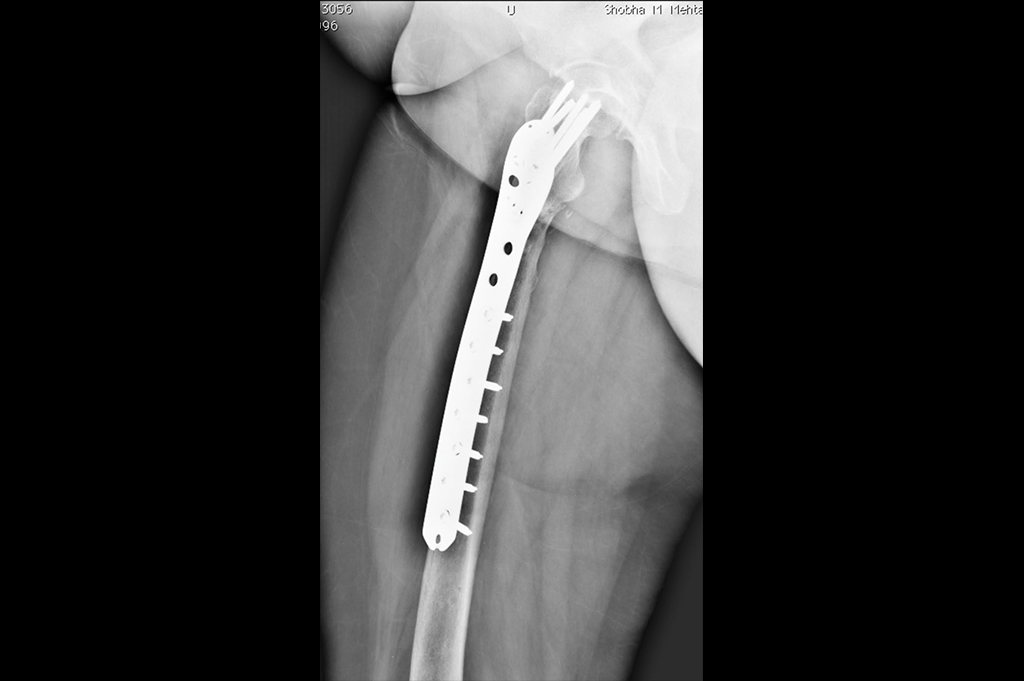

Subtrochanteric Fracture